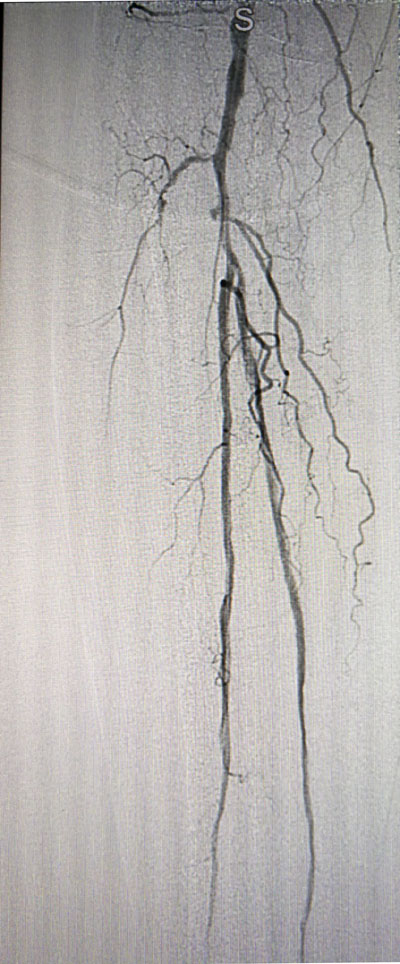

放射科导管室内做好了术前准备,患者由无创呼吸机及各种循环支持下开始介入手术,术中重症监护科严密观察患者的生命体征,内分泌科医生负责手术,患者下肢血流极差,膝下仅存一条多处严重狭窄的腓动脉供血,主要供血的胫前动脉及胫后动脉均长段闭塞,顺行穿刺成功后导丝下行困难,故采用踝下胫后动脉逆穿对接技术成功通过病变。经过近5个小时的奋斗,手术顺利完成,患者腓动脉及胫后动脉血流通畅,血流直达足底动脉环,患者感到足部逐渐温暖,术后清创时患者创面血流丰富。

治疗后